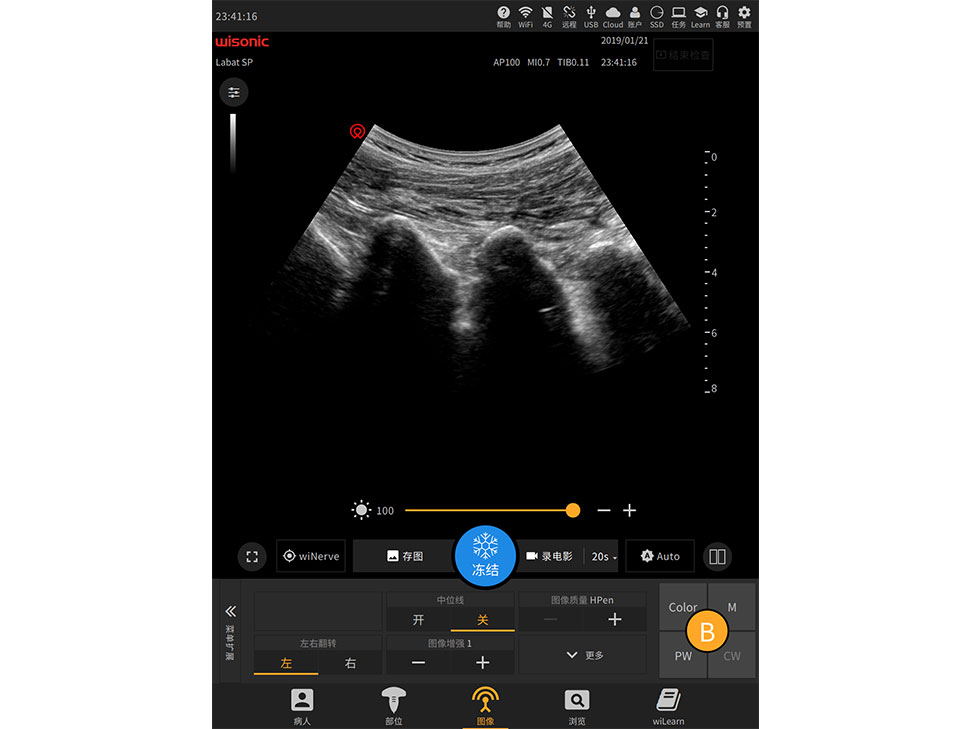

Labat

Excellent Clinical Images

Application pictures